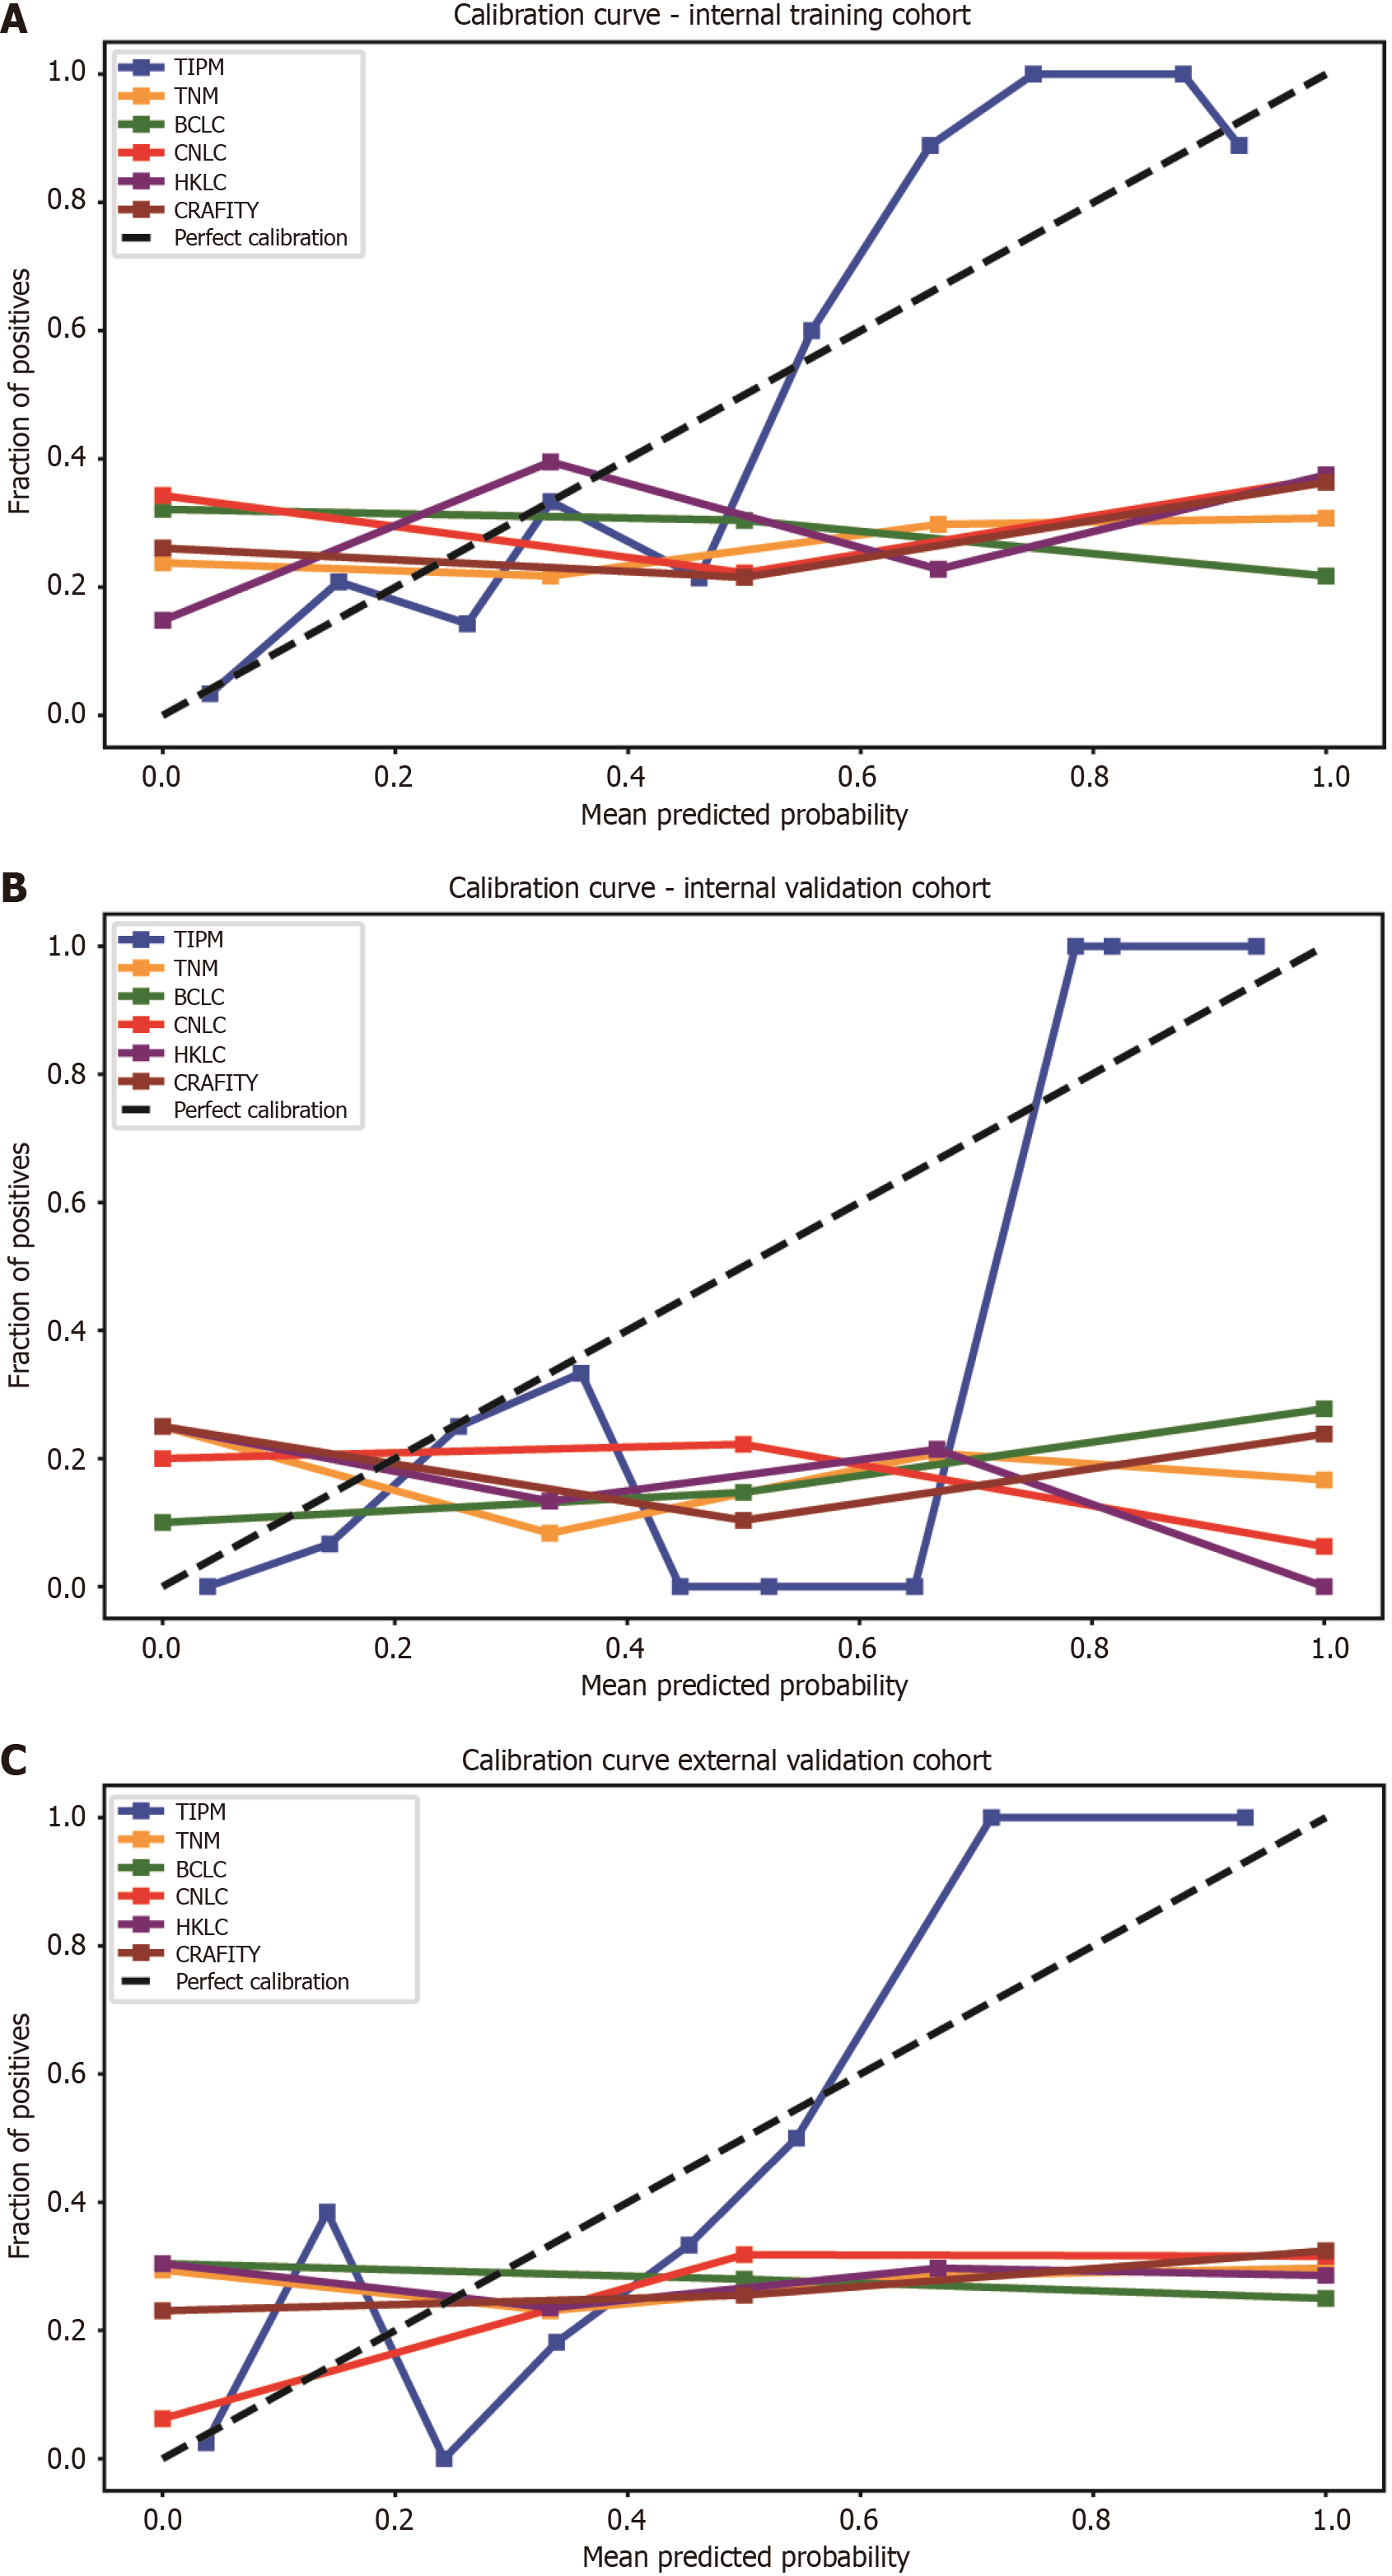

Figure 5 Calibration curves for model performance across cohorts.

A: In the internal training cohort, the Target Immunotherapy Predictive Model (TIPM)’s calibration curve closely followed the diagonal line, indicating strong agreement between predicted and observed probabilities. Other models exhibited greater deviations from ideal calibration; B: In the internal validation cohort, the TIPM model demonstrated good accuracy across both high- and low-incidence regions, though it slightly overestimated risk in the central region; C: In the external validation cohort, TIPM closely followed the actual curve, showing better calibration than other models, while conventional models tended to overestimate patient risk. TIPM: Target Immunotherapy Predictive Model; TNM: Tumor-node-metastasis; BCLC: Barcelona Clinic Liver Cancer; CNLC: China Liver Cancer; HKLC: Hong Kong Liver Cancer; CRAFITY: C-reactive protein and alpha-fetoprotein in immunotherapy.